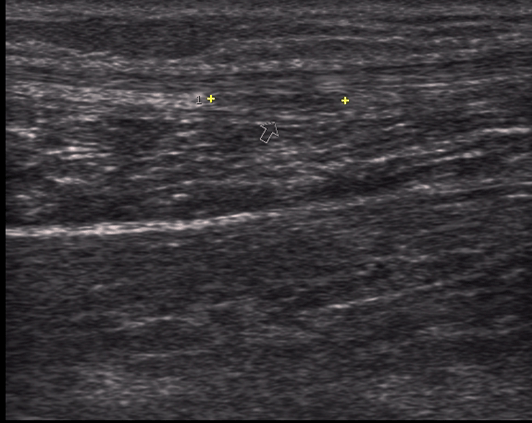

Tear of the musculotendinous junction of an achilles tendon Gepost op 11 juni 2017 door netwerkvsseh Tear of the musculotendinous junction of an achilles tendon @ theultrasoundsite.co.uk Dit delen: Delen op X (Opent in een nieuw venster) X Share op Facebook (Opent in een nieuw venster) Facebook Delen op LinkedIn (Opent in een nieuw venster) LinkedIn E-mail een link naar een vriend (Opent in een nieuw venster) E-mail Afdrukken (Opent in een nieuw venster) Print Vind-ik-leuk Aan het laden... Gerelateerd